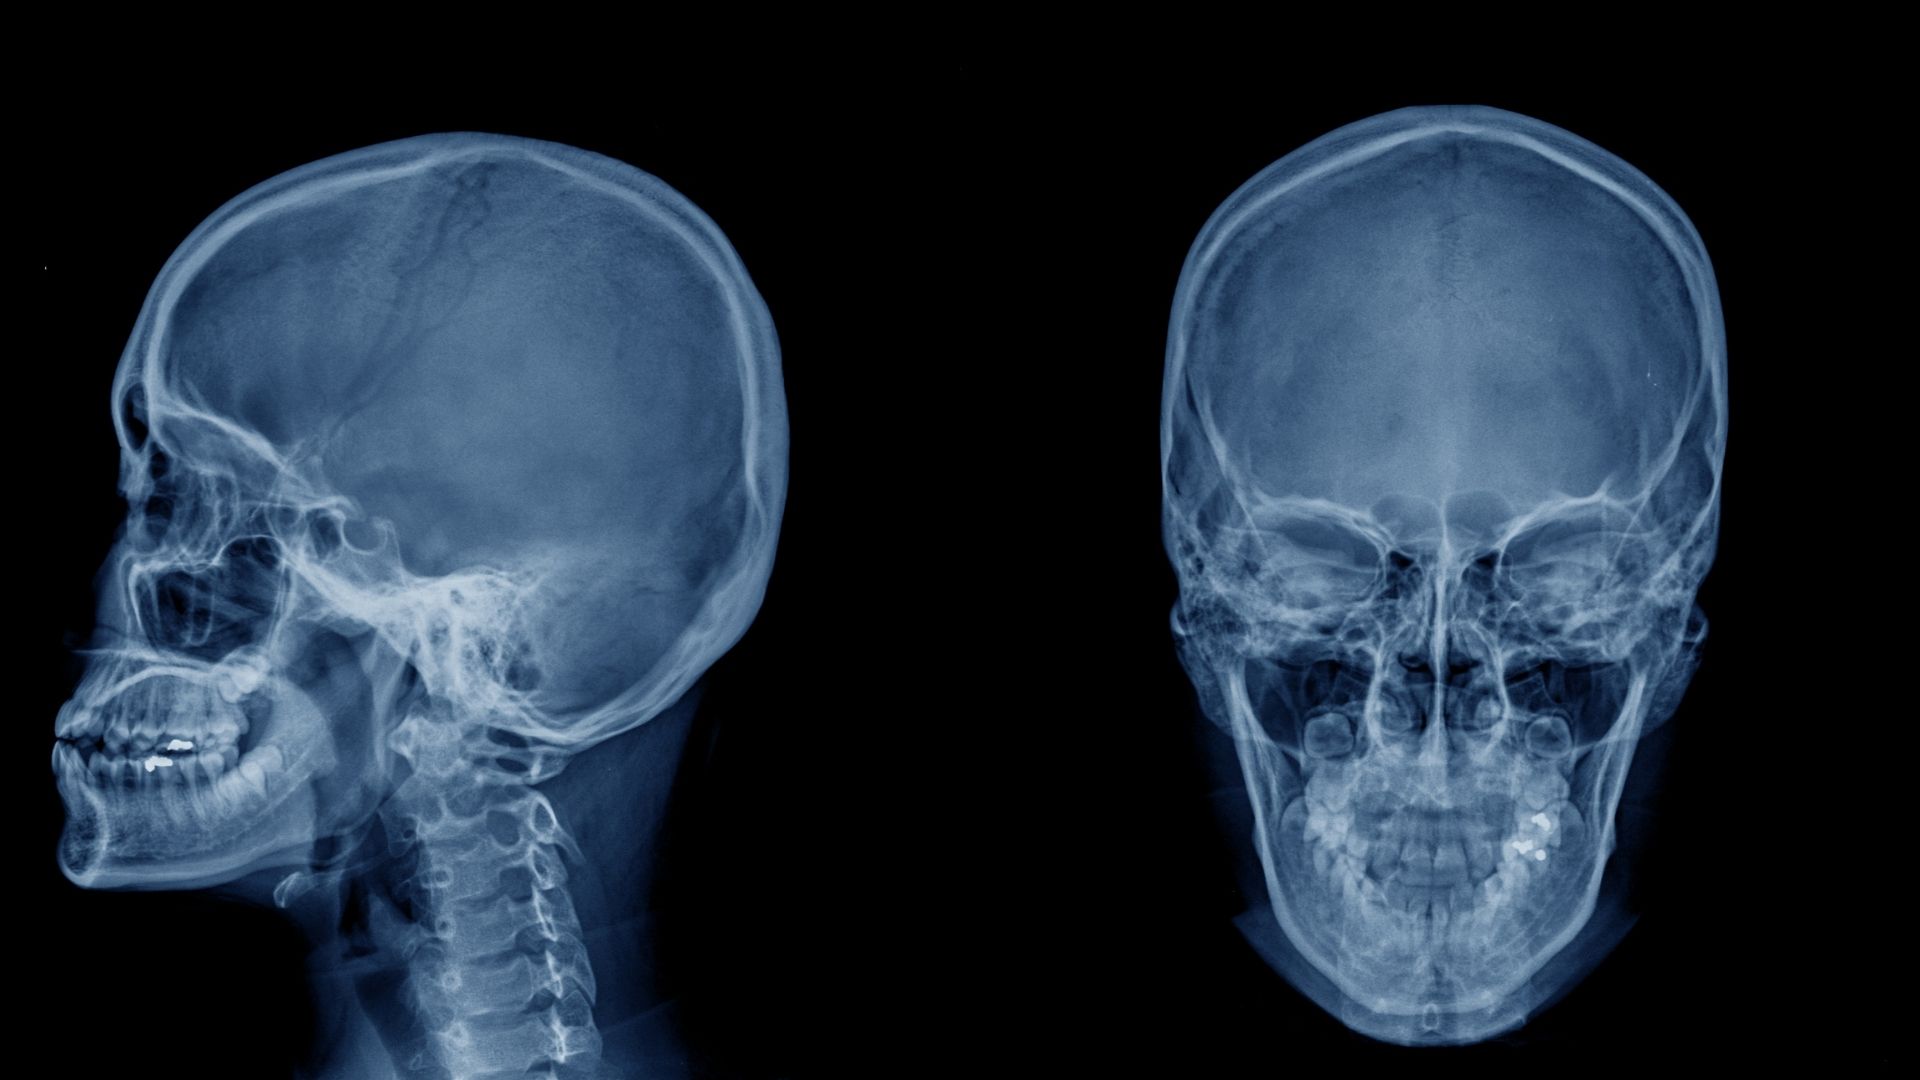

Chụp X-quang đầu là kỹ thuật chẩn đoán hình ảnh sử dụng tia X để ghi lại hình ảnh các cấu trúc xương vùng đầu, bao gồm xương sọ và một số vùng liên quan. Thông qua hình ảnh thu được, bác sĩ có thể quan sát hình dạng, cấu trúc và phát hiện những bất thường ở xương, từ đó hỗ trợ chẩn đoán ban đầu.

X-quang đầu có giá trị trong việc phát hiện các tổn thương liên quan đến xương sọ. Bác sĩ có thể nhận biết tình trạng nứt, gãy hoặc biến dạng xương sau chấn thương. Trong một số trường hợp, hình ảnh X-quang còn giúp phát hiện dị vật cản quang nằm trong vùng đầu, đặc biệt là sau tai nạn.

Tùy theo mục đích chẩn đoán, bác sĩ có thể chỉ định chụp X-quang đầu ở một hoặc nhiều tư thế khác nhau. Tư thế chụp thẳng giúp đánh giá tổng quan cấu trúc xương sọ và phát hiện các tổn thương rõ rệt. Tư thế chụp nghiêng hỗ trợ quan sát những vùng khó nhìn thấy ở tư thế thẳng, đặc biệt là các khe xương hoặc vùng phía sau đầu.